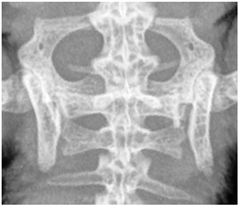

For this study, exclusively skeletal structures were examined. Four different structures (femur, ribs, vertebra, and phalanx) were chosen based on different bone architecture or features such as the differentiation of bone to soft tissue and surroundings (Table 3). The femur was essentially chosen to evaluate the differentiation between corticalis and spongiosa, joint structures were evaluated based on the left front phalanx, and the last left rib was used to further evaluate the details and structure of the corticalis. For each anatomical structure, four different characteristics (Table 3) were evaluated using a four-scaled scoring system, ranging from 1 (optimal evaluation) to 4 (insufficient evaluation). Scoring systems were used according to the modification of Körner, M. et al. [25] (Table 4).

In all four criteria, comparisons of D25% to D100% reached significantly lower scores than the D50% to D100%. The only exception was the phalanx using the CRP, but this was still nearly significant. The ribs showed the least significant difference between scores after the dose reduction. In both CR systems, a significant difference in scoring was only seen after the dose reduction from D100% to D25%, and in the FP system, a reduction from D100% to D50% already scored significantly different. The vertebra always scored significantly less with decreasing dosages independently of the radiography system used. For the phalanx, a dose reduction led to significantly lower scores in all comparisons for FP and CRN, but using the CRP, no significant difference was seen comparing the different dosages used. The femur showed different results with each system used. The CRN comparison of D50% to D25% showed no significant difference, while D100% to D50% and D100% to D25% did, with the latter even being highly significant. Using the CRP, only the comparison of D100% to D25% was significant, whereas while using the FP, every comparison of dosages showed a significant to highly significant difference in scoring (Table 5).

4.3. Effect of Dose Reduction

Data showed that in every system, a dose reduction led to significantly worse scores for most of the criteria, especially in the “double” reduction from 100% to 25%. Regarding the criteria, the vertebra seems to be the most sensitive structure with significantly worse scores after every reduction with each system used. In contrast, the ribs showed the least influence of the dose reduction, only receiving decreased scores after a reduction of 25%. The effect of dose reduction for the criterion femur varied. In the ribs and femur, the reviewers had to evaluate the differentiation between the bone, whilst in the criteria for vertebra and phalanx, the demarcation to the surrounding tissue and joint space was addressed. The vertebra and phalanx are much more delicate structures than the femur and rib, indicating a possible greater impact of dose reduction on smaller structures. In particular, the joint space with a fine surface and superimpositions of other structures could therefore be more affected than more solid structures such as the femur. The ribs are much more delicate than the femur, impeding the evaluation of this criterion and possibly leading to a greater impact in dose reduction, again indicating a greater influence on smaller structures. In contrast, the femur showed the best scores, indicating that the thicker and bigger the structure, the higher the chance of being able to evaluate variances.